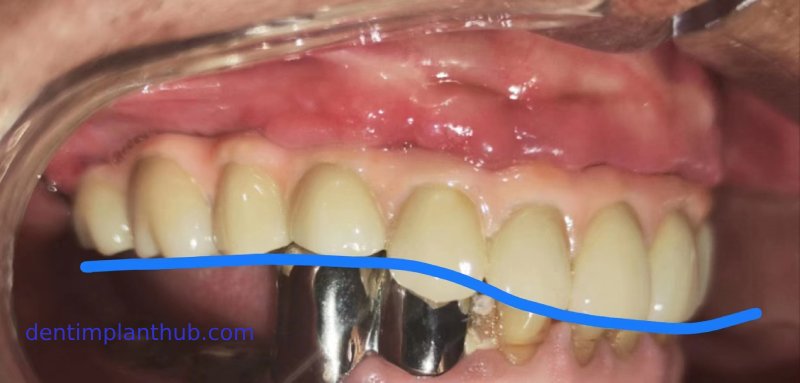

Photos of the temporary dental crown fabricated on the same day

Photos of the temporary dental crown placed in the mouth